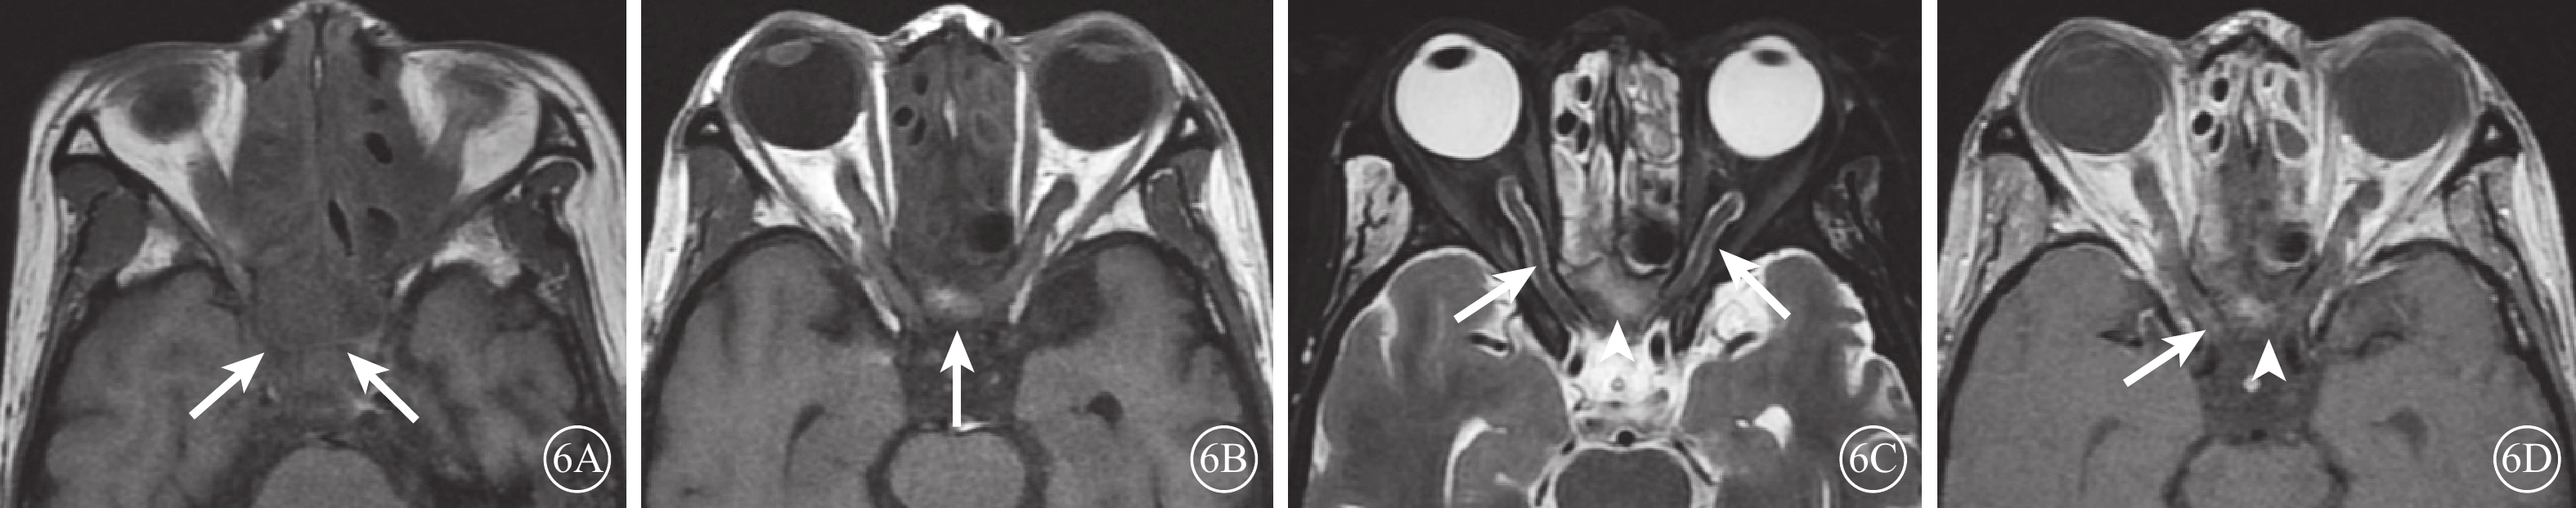

ION患眼,T2加權像視神經彌漫性或局限性增粗,伴或不伴鞘膜間隙增寬;T1加權像造影劑增強序列可見視神經鞘膜強化,其中軸位像示視神經呈雙軌樣強化(雙軌征),冠狀位像示視神經呈環形強化(袖套征),但視神經實質無明顯增粗或強化(圖5)。其中,繼發于全身性惡性腫瘤的13例17只眼中,合并眼外肌等眶內軟組織浸潤改變1例1只眼;繼發于眼眶周圍惡性腫瘤的7例9只眼,均可見與眶周原發性惡性腫瘤相延續、且累及視神經的軟組織腫物(圖6)。合并癌性腦膜炎的4例6只眼,均可見腦膜局灶性或彌漫性增厚和強化;合并顱內轉移灶的4例4只眼,均可見腦實質內散在分布的點狀或灶狀長T2信號病灶伴強化。